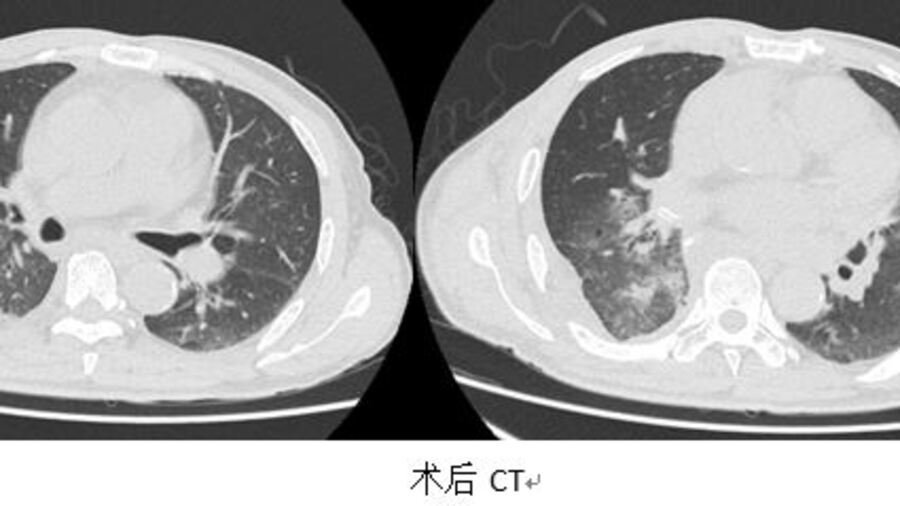

经过反复沟通、再三权衡,医患统一意见:确定手术切除!经过2小时的顺利手术,巨大肿瘤被完整切除,同时切除了两个肺叶,达到根治效果。术后,患者在ICU医护人员的精心照顾下,顺利脱离呼吸机,目前恢复良好,已经出院。

王明松说,虽然该病例较为特殊,但也提示广大中老年市民,胸部疾病大多有隐匿性,因此定期的常规体检非常重要,“普通人群应一年进行一次胸部CT检查,如已发现病灶,应遵循医生专业指导,做好更为短期的随访,切勿将鸡蛋大的肿瘤拖到西瓜那么大。”